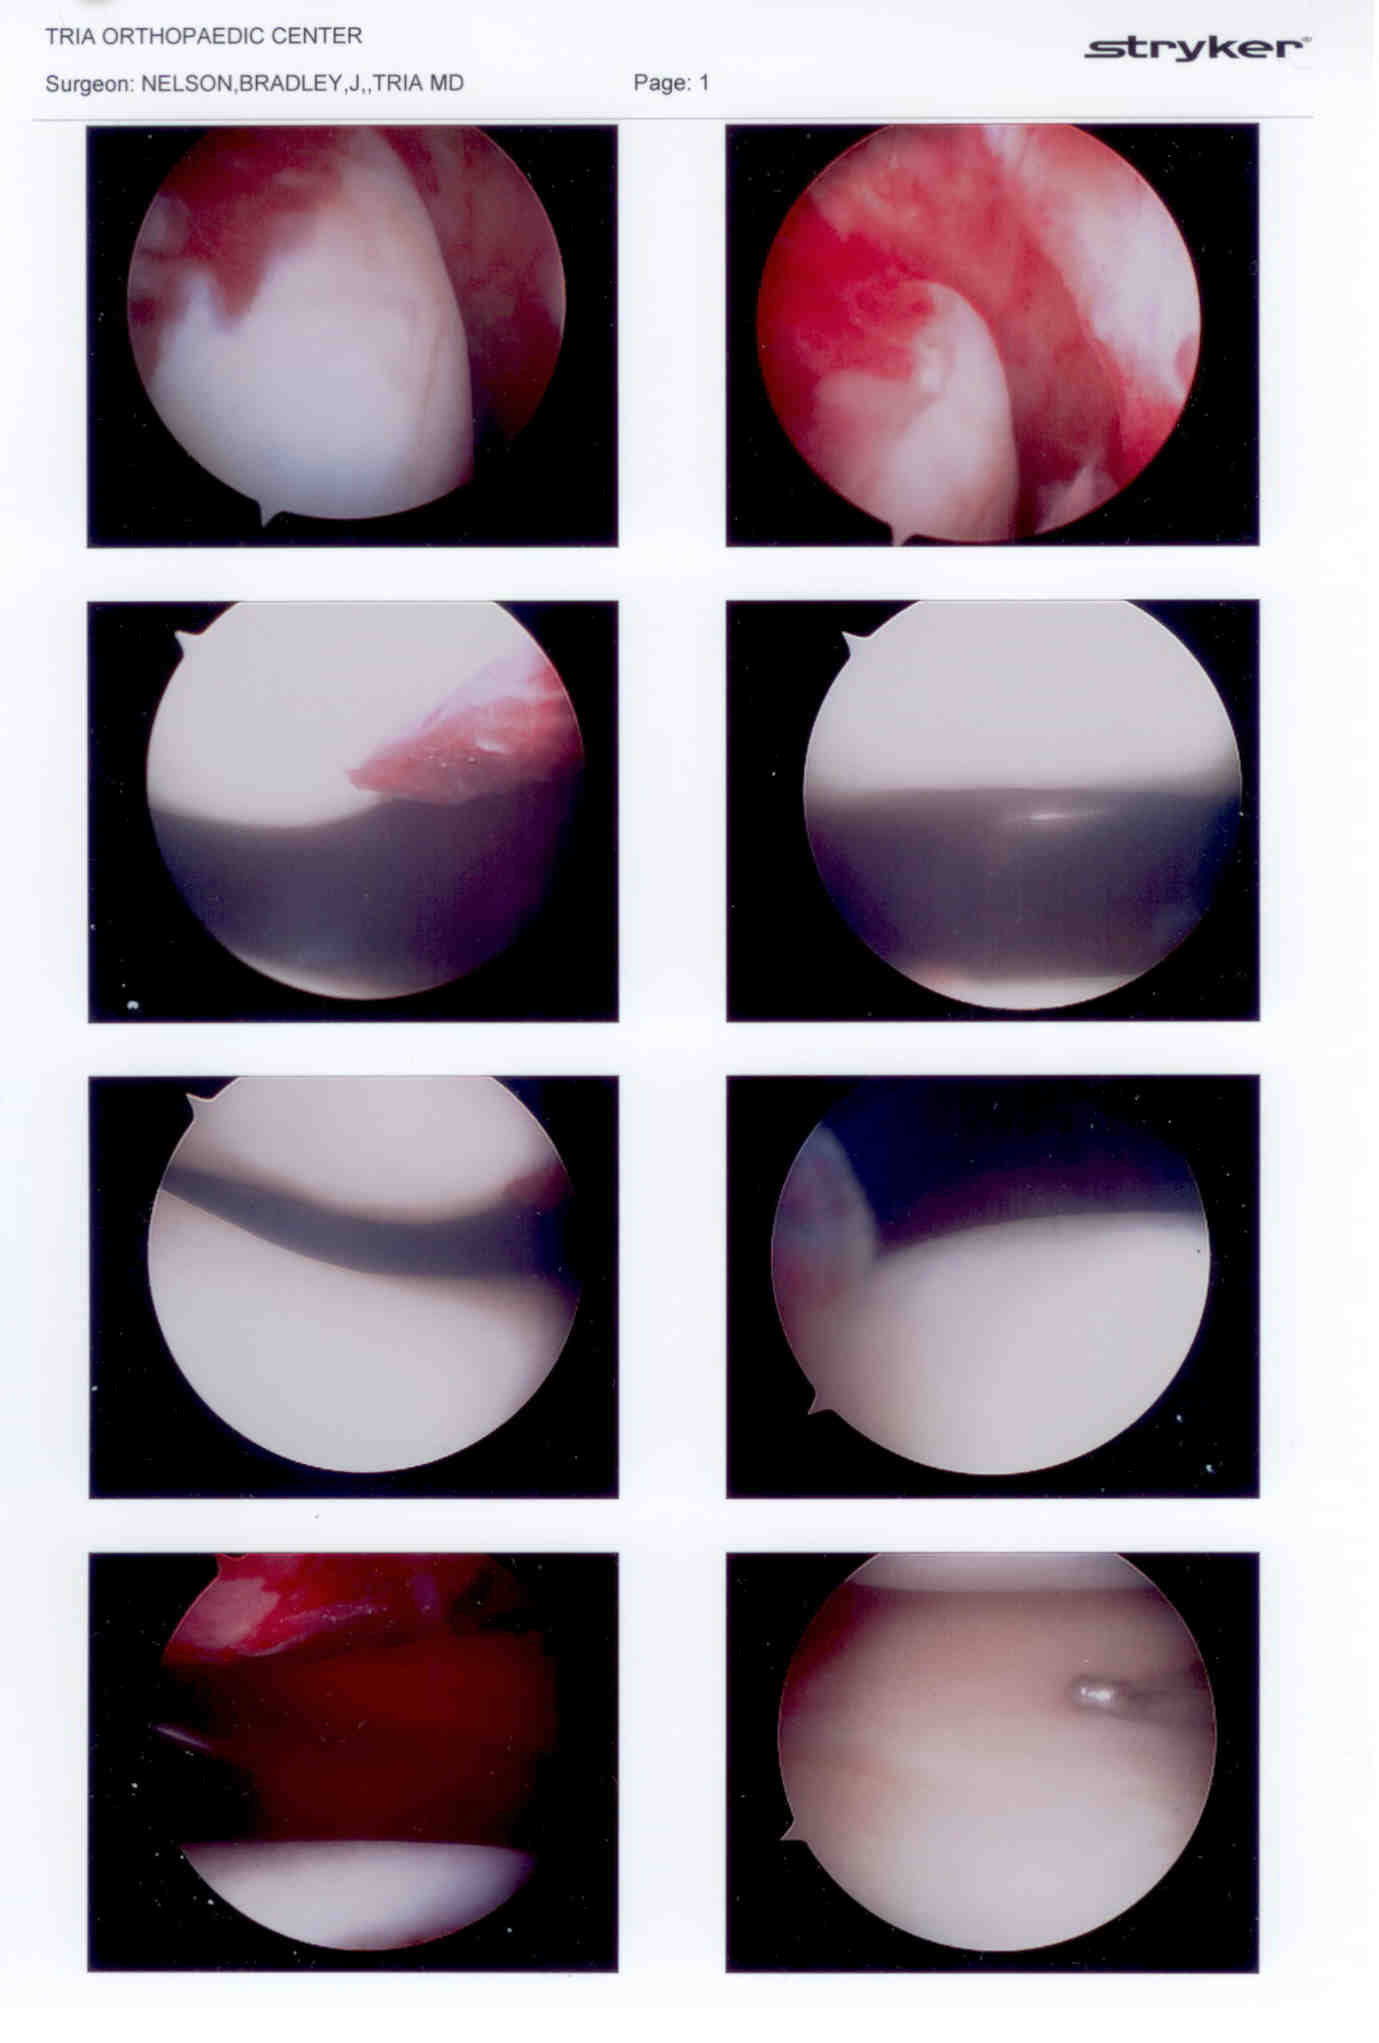

First set of pictures are the arthoscopy showing 2nd from top on left the area of blood clot from where the fragment was dislodged (119kb).

Second set are some arthroscopy, followed by full open knee and patella.  The bottom right shows the fragment with a pin holding it in place (141kb).

Truly an unfortunate, accidental injury from his opponent falling on first his foot to pin it to the mat, then the rest of this weight landing on the back of Kurtis calf as he was turning into him to complete the takedown.  Video may be posted later.  Injury was a high level (grade 3) tear of the MCL, a sprain of the medial meniscus ligament, consistent with patella dislocation resulting in an osteochodral fragment fracture.